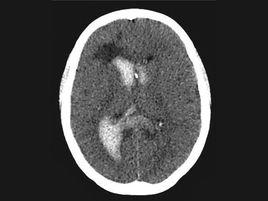

4.CT檢查:是非損傷性檢查方法,能明確血腫部位,可鑑別蛛網膜下腔出血與腦內血腫及後者是否穿破入腦室。